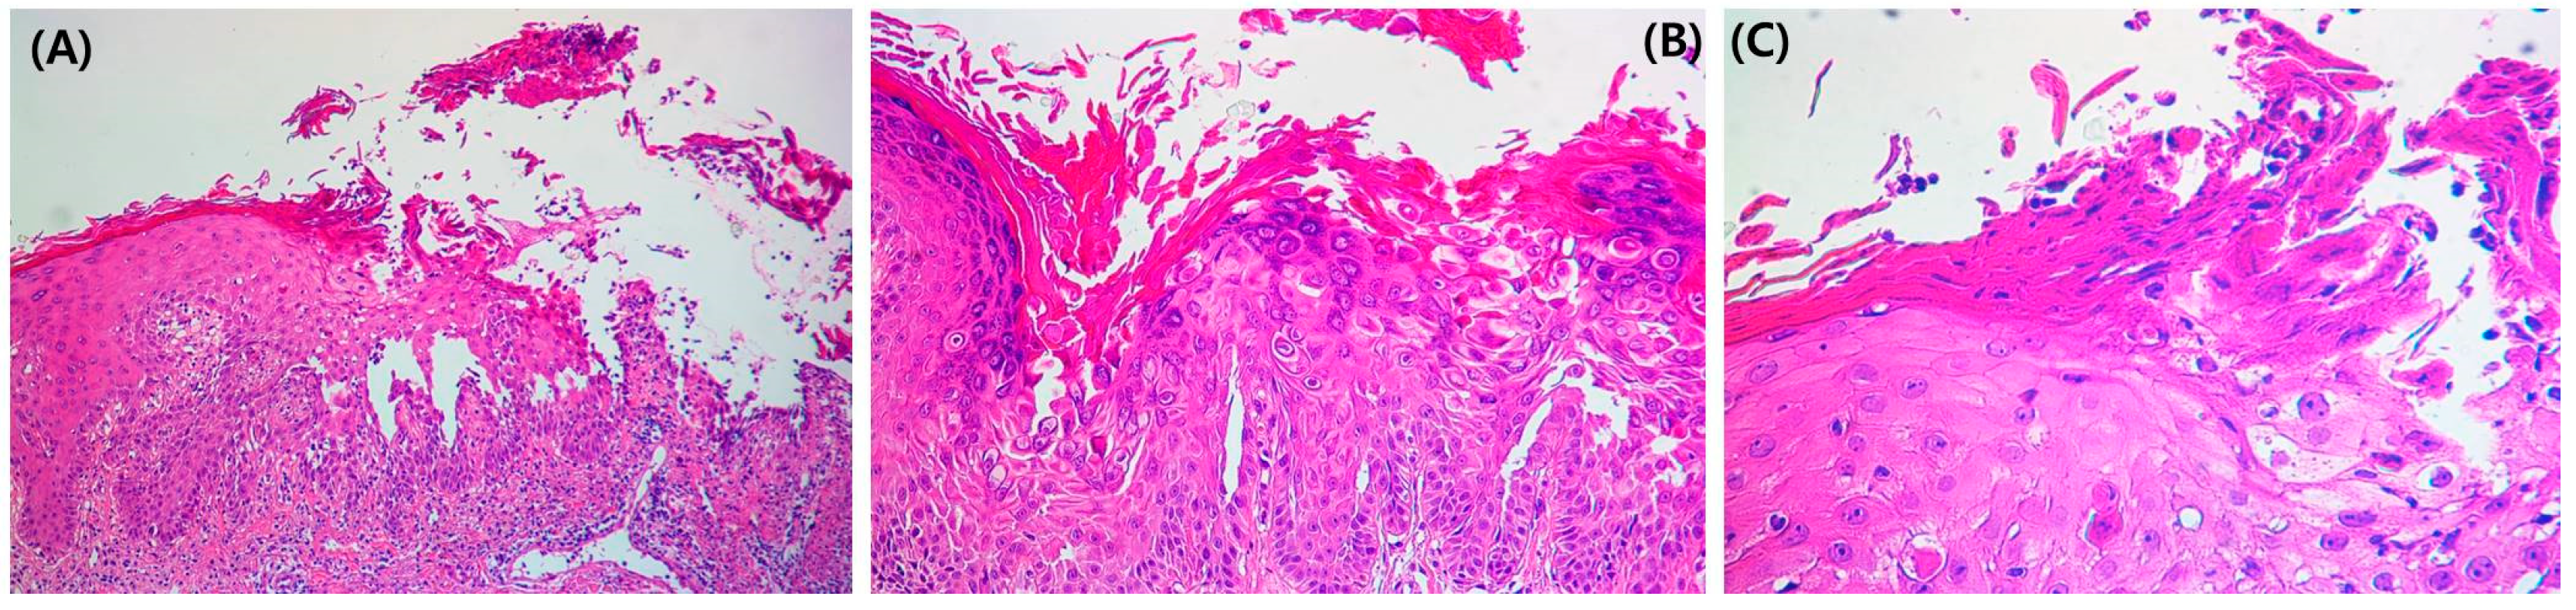

The treatment was changed to guselkumab, after which he improved for 4 months; however, the condition of the skin lesions waxed and waned repeatedly. A punch biopsy was performed on the abdominal lesion. Focal acantholysis was present in the suprabasal layer of the epidermal erosion area (Figure 3A). Dyskeratosis and corps ronds, pyknotic nuclei, and a clear perinuclear halo (Figure 3B) were observed in the epidermis. Corps grain compressed cells with elongated nuclei were seen in the stratum corneum and granular layer (Figure 3C).

Figure 3.

(A) Focal acantholysis was present in the suprabasal layer of the erosion area in the epidermis (H&E 100×). (B) Dyskeratosis and corps ronds, pyknotic nuclei, and a clear perinuclear halo (H&E 200×) were observed in the epidermis. (C) Corps grain compressed cells.